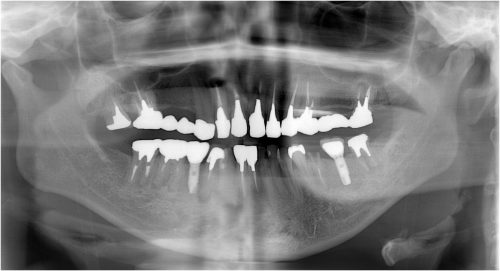

左下奥歯 欠損部 写真

術 前

被せ物装着後

川口で精密インプラント治療なら さかえ歯科クリニック